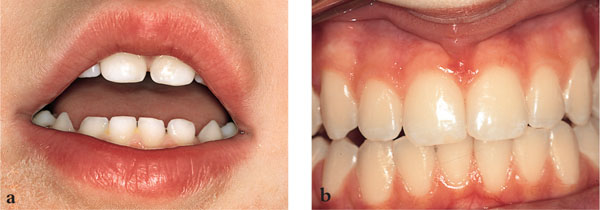

Fig 1-3 Caries-free child with (a) primary teeth and (b) permanent teeth.